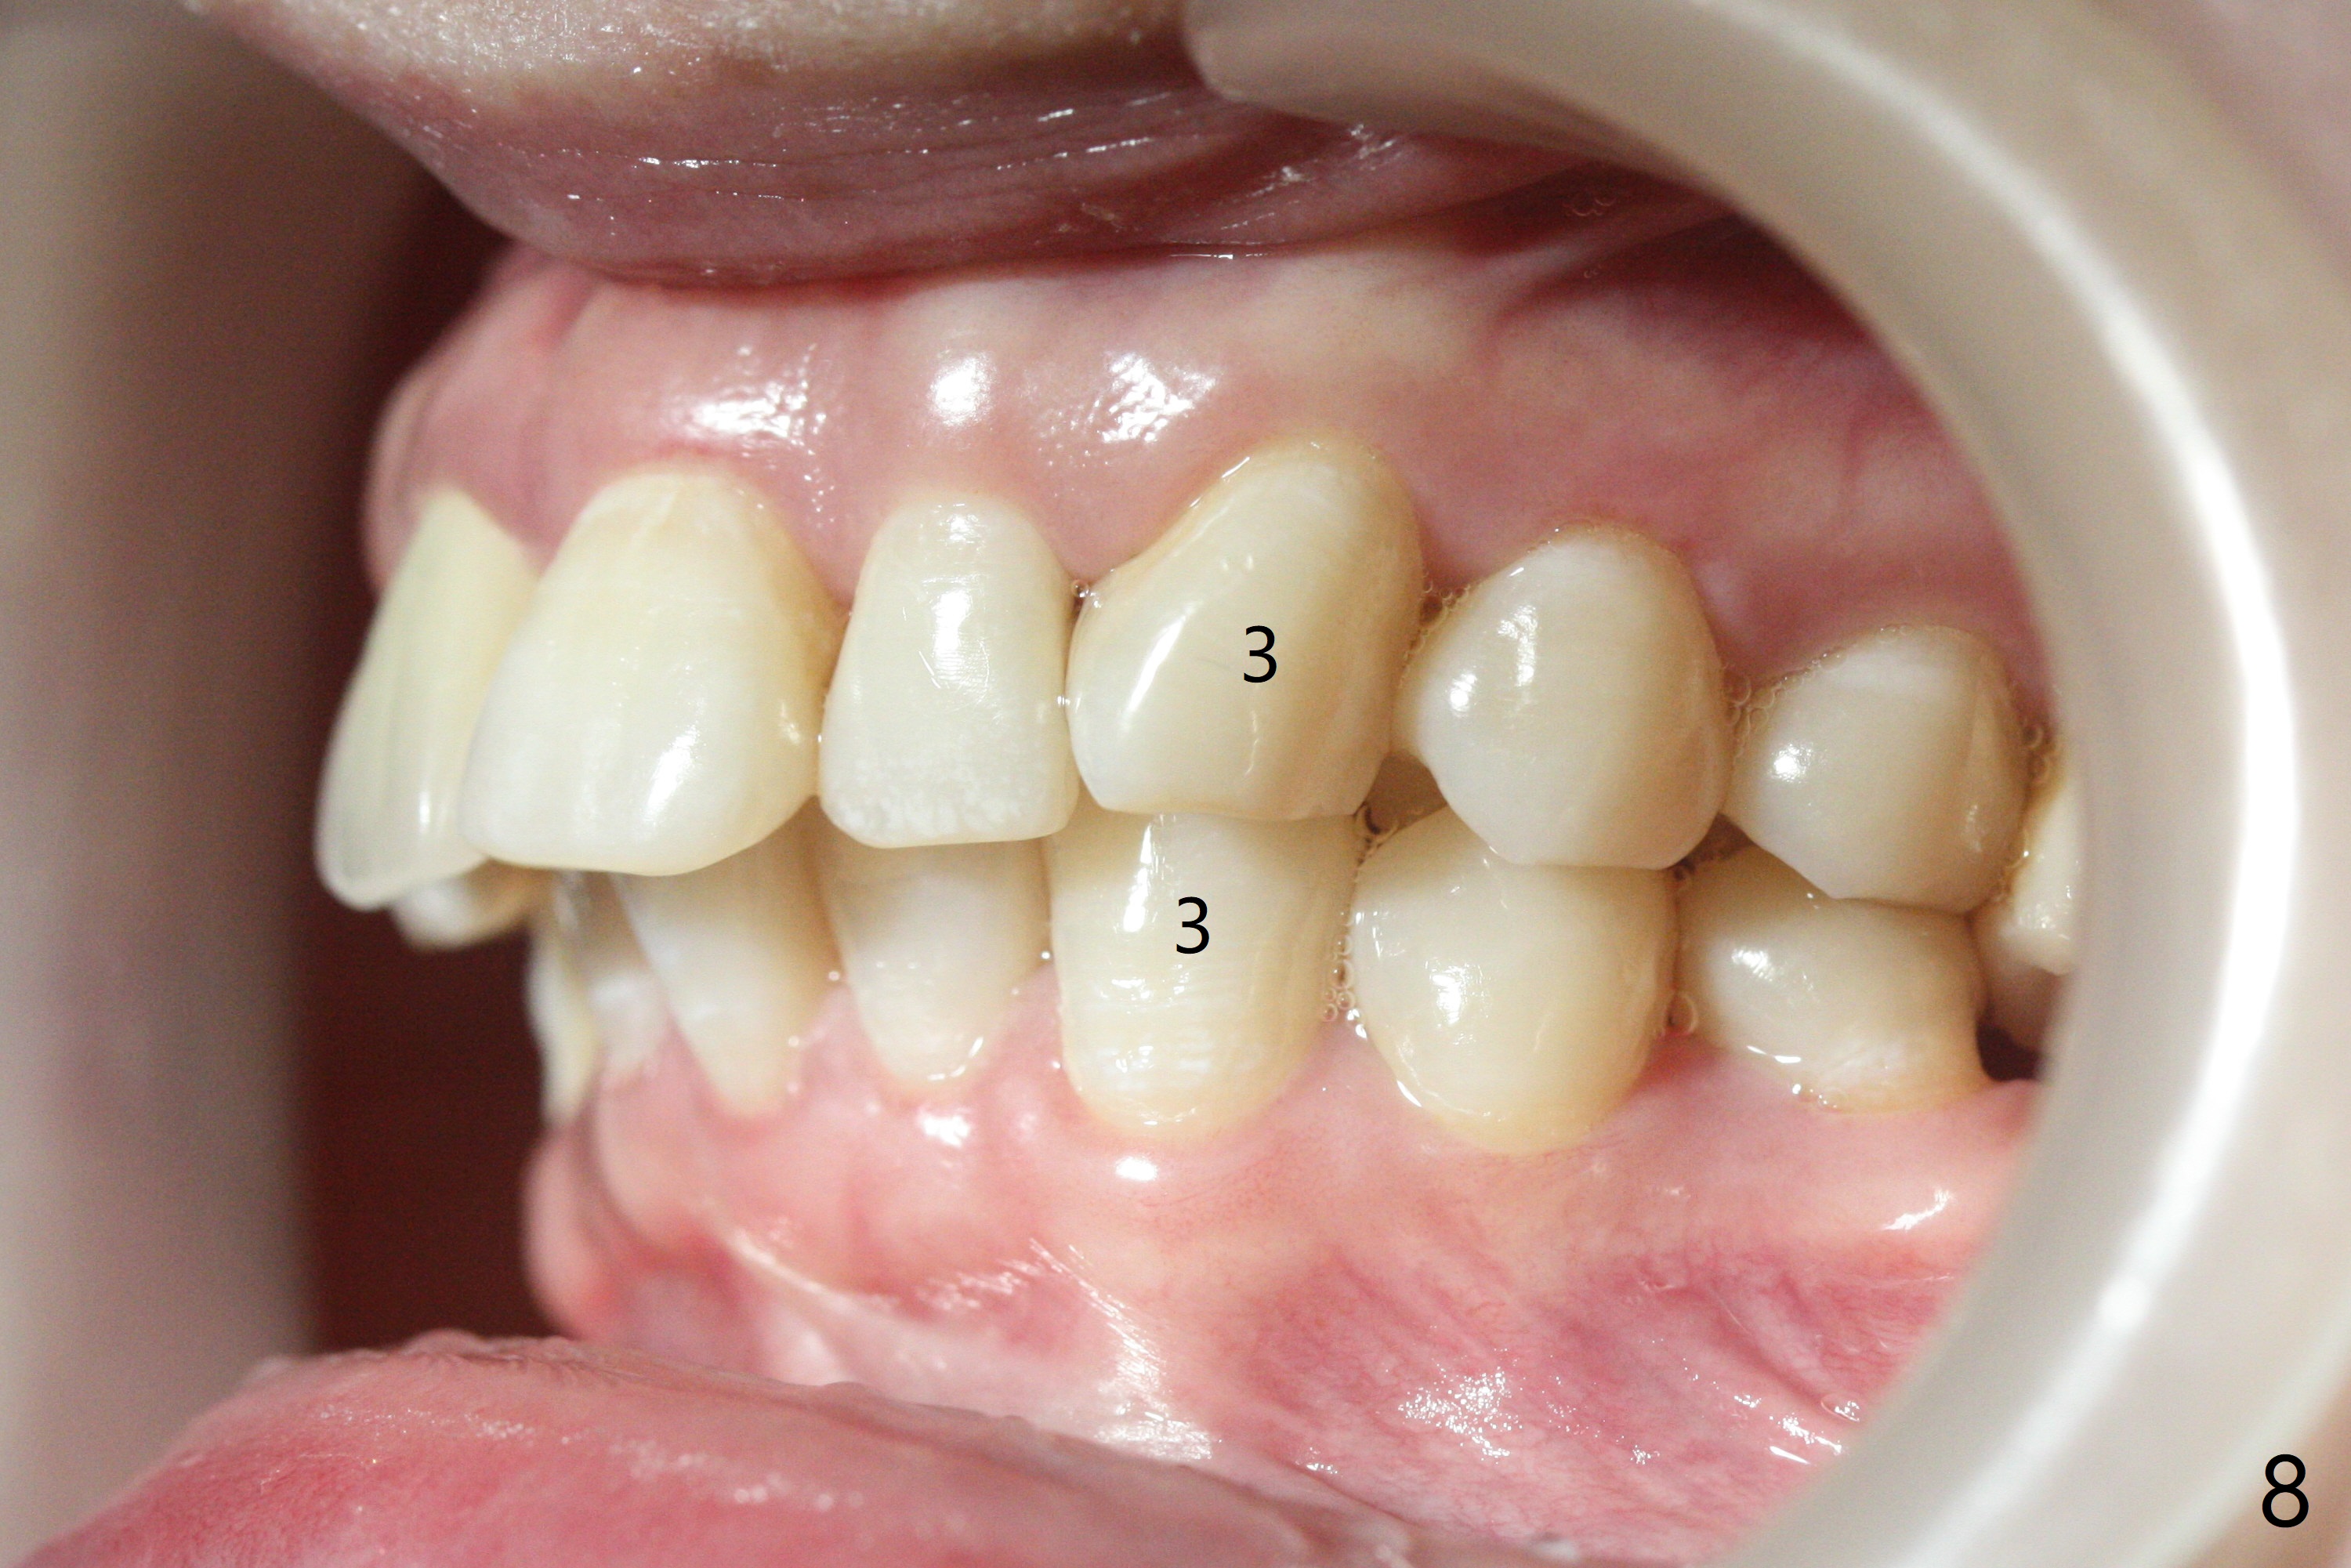

31岁女面部还匀称(图一,二,四,五),但是二类错𬌗严重(图三,六至十),应尽早做二类牵引。压低左上6是 头等大事。磨牙间隙不容易产生,为了避免矫正后磨牙间隙问题,不放置磨牙bands,在右上,右下6,左上6,7放置矫正器,再次使用12niti弓丝。